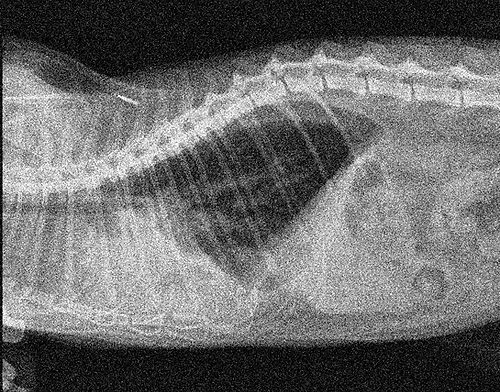

Abaixo, temos um exemplo de baixo rendimento do tubo de raios-x:

IMAGEM RUIDOSA

Durante exposições repetidas prolongadas das placas CR ou detectores DR, a qualidade da imagem começa a se degradar, tornando cada vez mais difícil para os médicos determinarem onde uma estrutura anatômica começa, e a outra termina.